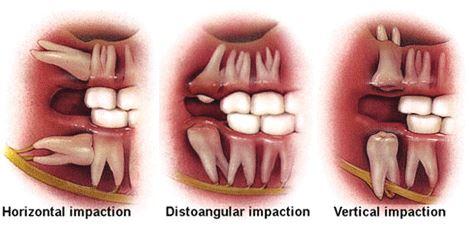

Wisdom teeth are the last tooth behind the upper and lower second molars, and usually appear during a person's late teens or early twenties. When a wisdom tooth is blocked from erupting or coming into the mouth in its normally position, it is termed "impacted"

Serious problems may develop from impacted teeth, such as pain, infection, crowding of, or damage to adjacent teeth. Sometimes more serious problems can occur if the sac that surrounds the impacted tooth fills with fluid and enlarges to form a cyst. This enlargement can hollow out the jaw and result in permanent damage to the adjacent teeth, jawbone and nerves. If the cyst is not treated, a tumor may develop from the walls of the cyst and a more involved surgical procedure may be required for removal. Many problems with wisdom teeth may occur with few or no symptoms, so there may be damage without you knowing it.

Treatment of impacted wisdom teeth involves their removal using special surgical techniques and instruments appropriate for each individual case. Dr. Smith is a dentist who has specialized training in the removal of wisdom teeth and is a Board Certified Oral and Maxillofacial Surgeon. With modern anesthesia technology, it is now possible to perform these procedures in the dental office safely while you sleep, so there is little or no discomfort to you. Most teeth can be removed in an office setting, painlessly and with a short recovery period.